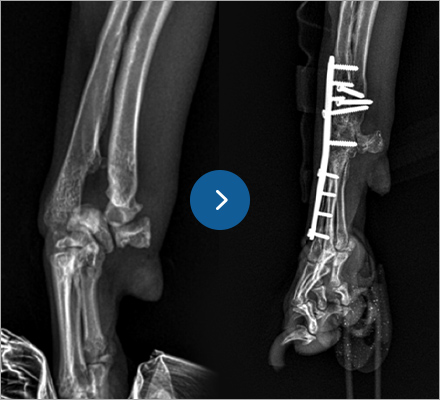

골절수술

- 요척골 단순골절

- 4살, 이탈리안그레이하운드

고난이도 상완골 원위부 골절

- IOHC, 상완골과골절

- 4개월 시추 2.6kg

고난이도 소형견 골절 수술

소형견 슬개힘줄 단열

- 무릎 관절고정수술

- 6살 포메라니안, 3.0kg

소형견 고난이도 수술 진행

테디 수술 전

테디 수술 3주 후